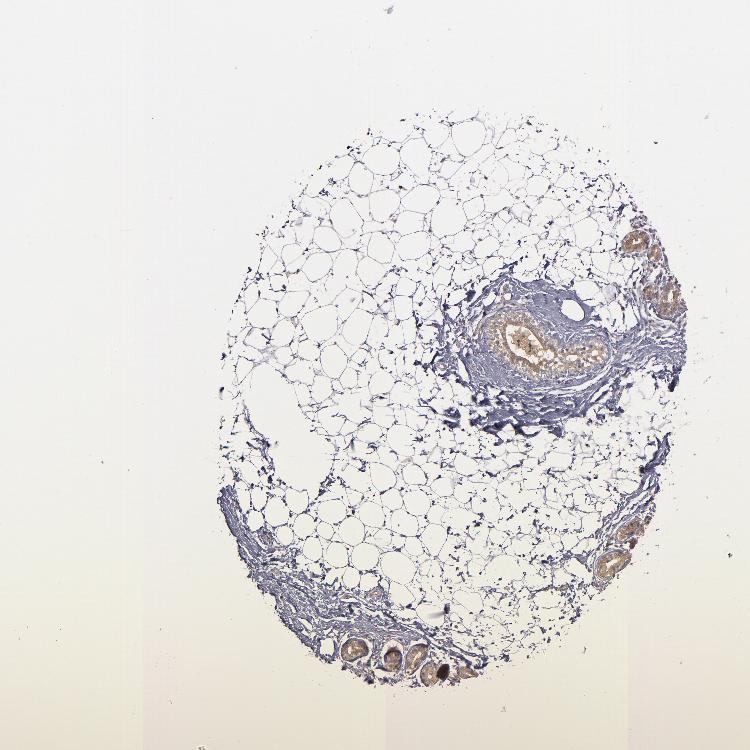

SOFT TISSUE 2 - Antibody stainingi

Antibody staining in the annotated cell types in the current human tissue is reported as not detected, low, medium, or high, based on conventional immunohistochemistry profiling in selected tissues. This score is based on the combination of the staining intensity and fraction of stained cells.

Each image is clickable and will lead to virtual microscopy that enables deeper exploration of all samples and also displays staining intensity scores, fraction scores and subcellular localization as well as patient and tissue information for each sample.

Antibody HPA002803

Fibroblasts Low

Peripheral nerve Not detected